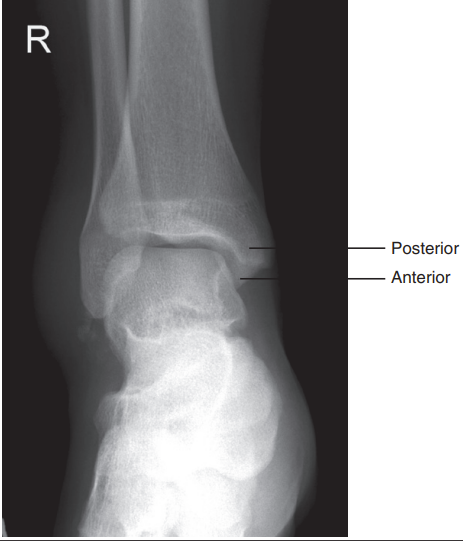

Posterior and anterior tibial margin can be seen

Distal leg is elevated

Medial mortise is closed, and anterior tibial margin has been projected proximal to the posterior margin

Distal tibia has been elevated

What are the issues with this ankle?

Foot is not dorsiflexed